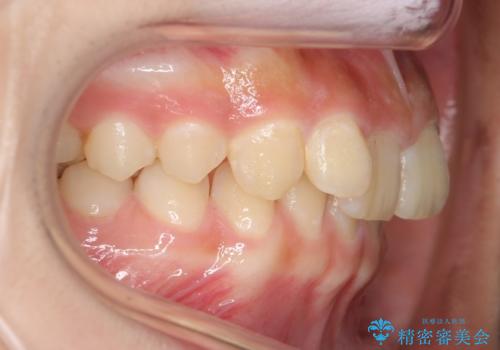

前歯のがたつき 過蓋咬合

今回は上の前歯が内側に傾いている症状があり(Angle Ⅱ級2類)、その修正に時間がかかっています。

奥歯のかみ合わせが、歯と歯が向かい合わせになっておりまた、歯ぎしりも多い方で装置の脱離も頻繁にありました。

ワイヤー矯正ではやや難しい症例でした。